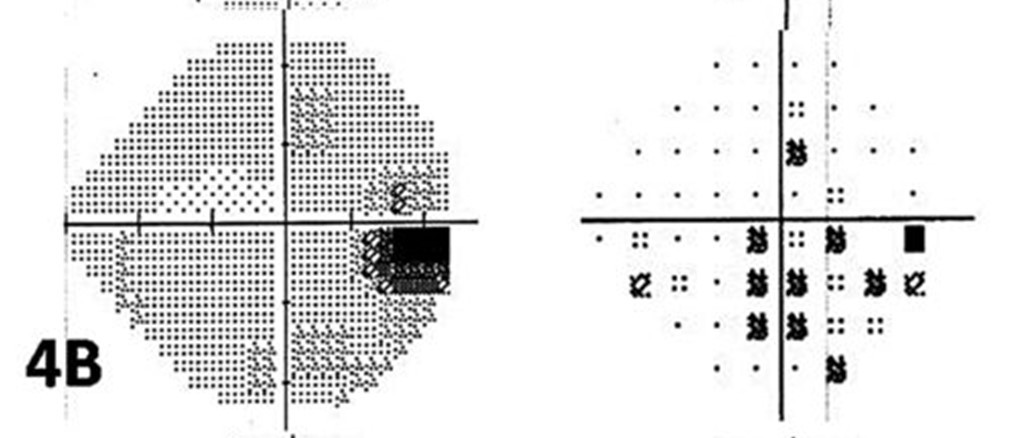

early superior paracentral defect at 10 degrees

established superior arcuate defect

Nasal step

superior arcuate with peripheral breakthrough and early inferior defect

superior, fixation threatening paracentral defect

temporal wedge

tunnel vision defect with temporal crescent sparing

Advanced arcuate

Early arcuate